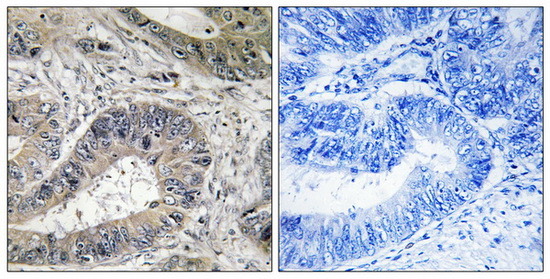

Supportive validation

- Submitted by

- Aviva Systems Biology (provider)

- Main image

- Experimental details

- Immunohistochemistry analysis of paraffin-embedded human colon carcinoma tissue, using ERN2 antibody. The picture on the right is treated with the synthesized peptide.